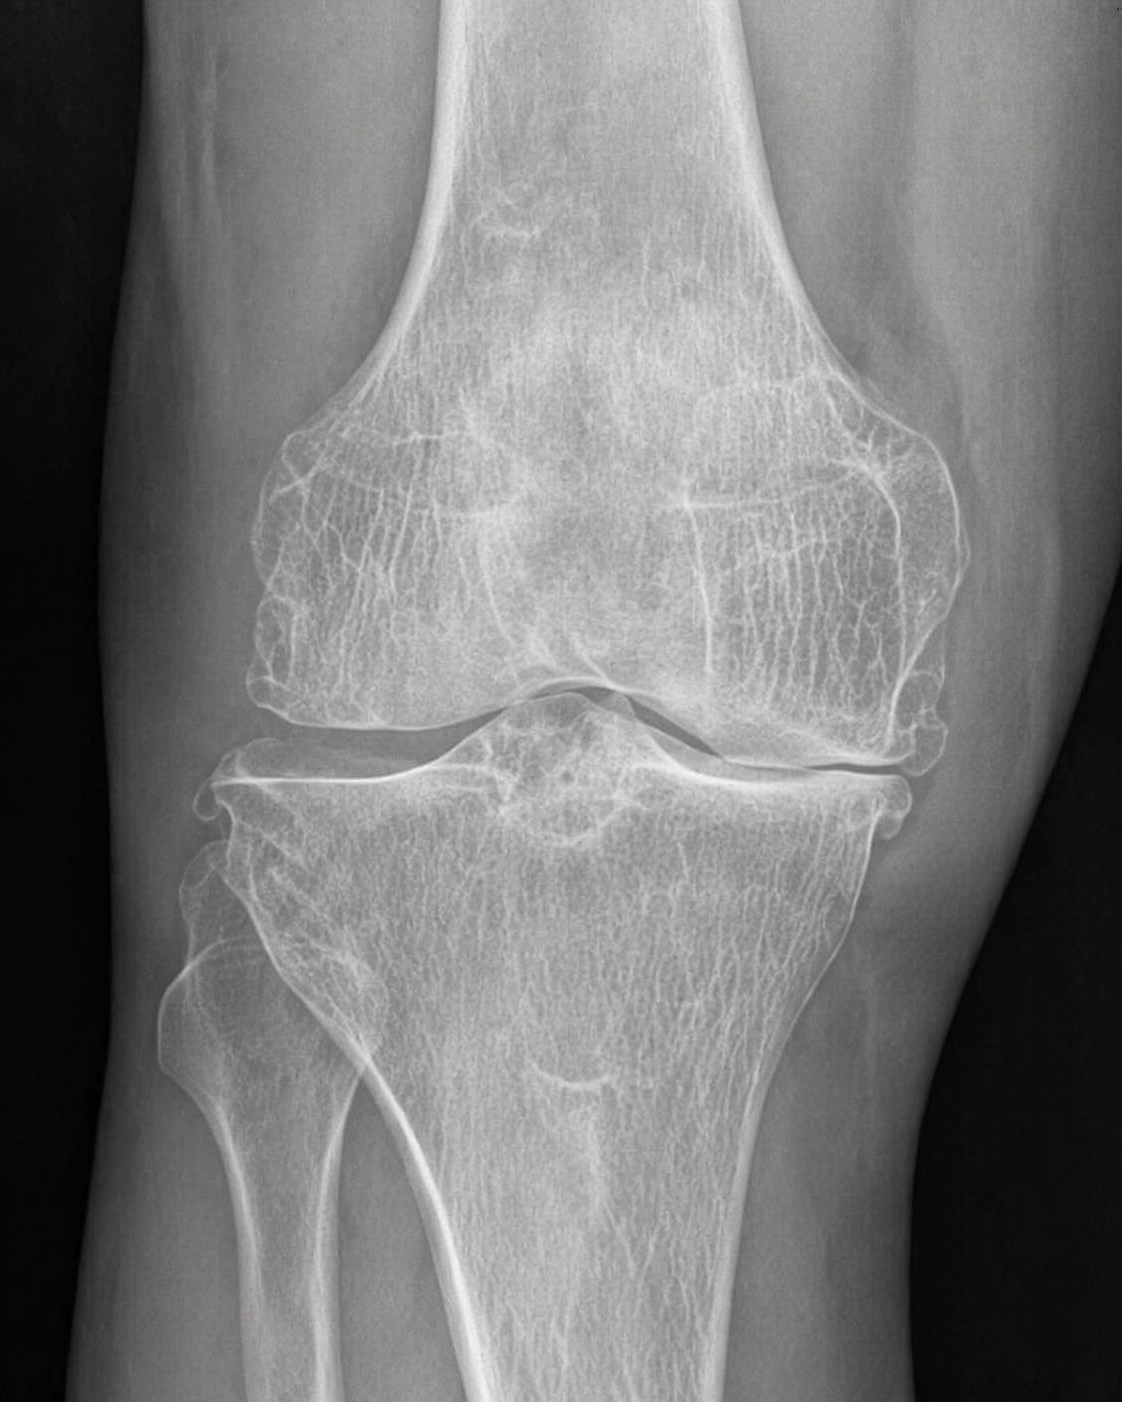

With the help of orthopedic doctors, I was able to diagnose one of the causes of my knee pain. I had a case of mild arthritis. Over the years and at my check-up about four years ago, I was told it was more like mild to moderate. About a year ago, I re-did X-rays and MRI. The knee cartilage showed degenerations in all three compartments and so the doctors started to characterize my knee arthritis as moderate to severe.

I got a referral to a physiatrist, who manages pain without surgical interventions. Upon examination, the first thing he did was to get a knee X-ray and MRI of my lower back. X-ray showed moderate to severe degeneration of the knee cartilage. MRI showed degeneration of my cartilage between my L4 and L5 and S1. He recommended an epidural injection to the lumbar to “calm” any inflammation and then reassess.